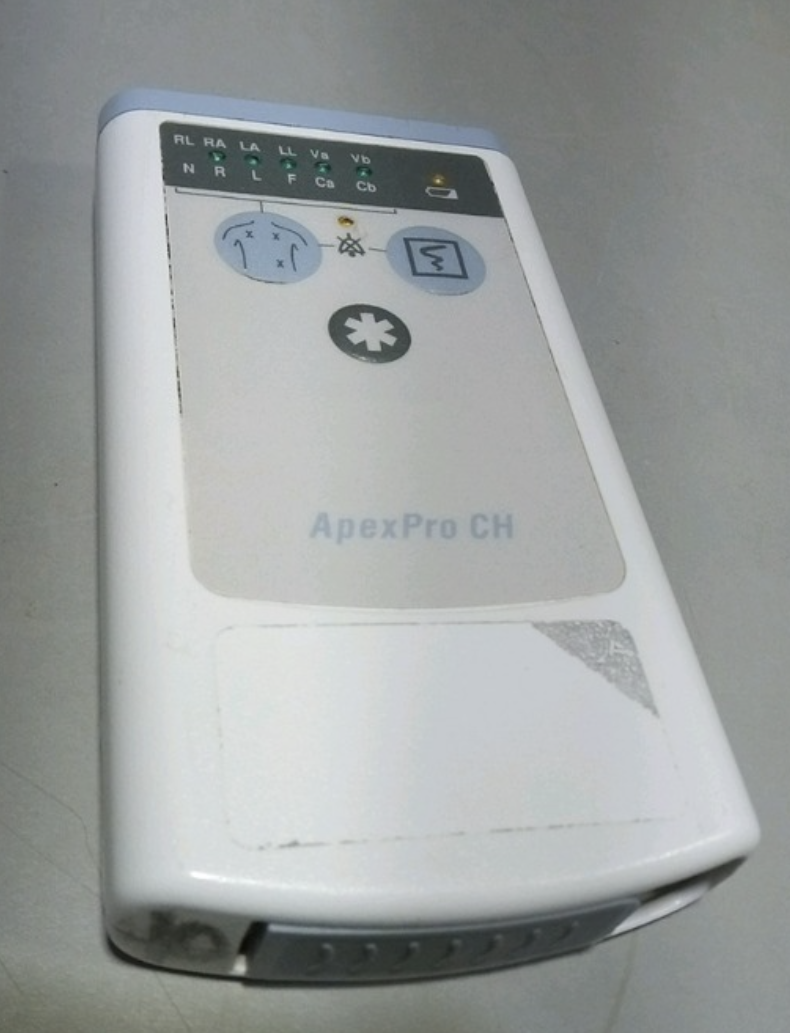

GE APEX PRO CH HANDHELD PATIENT MONITOR APEXPRO

Sale price$ 1,810.80